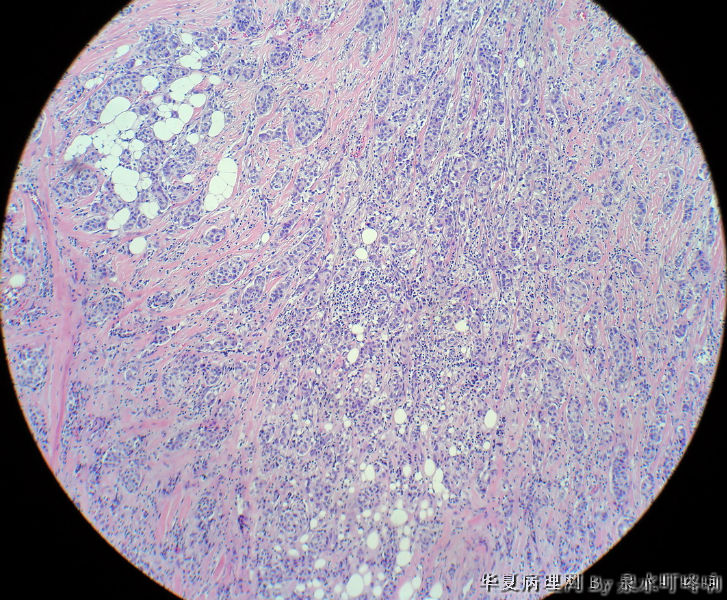

右腋下包块

最后诊断:浸润性导管癌(分化较低),考虑来自乳腺尾叶或副乳恶变。

乳腺浸润性导管癌首先考虑乳腺转移。

乳腺浸润性导管癌

乳腺来源的浸润性导管癌,至于是乳腺癌转移而来还是副乳发生,应该结合临床病史和其他检查结果来综合判定,不是单纯依靠病理切片可以判断的。